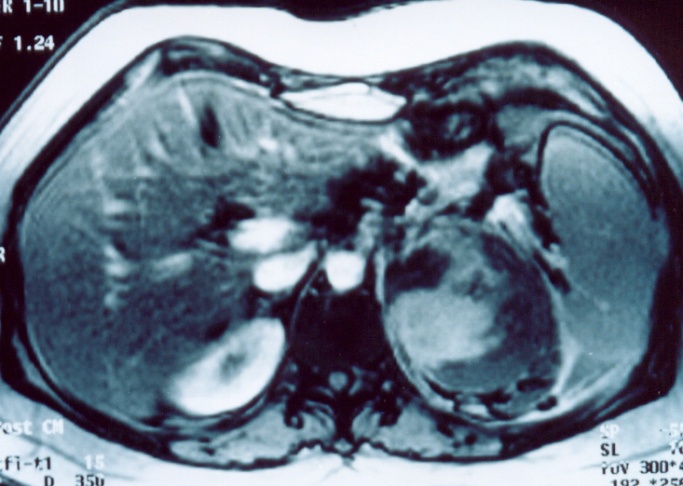

Αμφοτερόπλευρη αυτόματη νεφρική αιμορραγία — κοκκιωμάτωση Wegener (Ευγενική παραχώρηση Dr. V. Penopoulos)